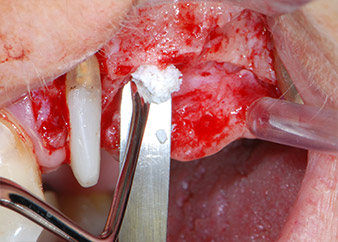

Prior to implant placement, infected tissue was removed from the alveolar bone in the implant site and around the abutment teeth with an insert originally designed for bone shaping and collecting bone chips (Piezomed, insert B5) (Figs. 6 and 7).

piezo-electric scraping instrument

Fig. 6: The surgical site was debrided with a piezo-electric scraping instrument designed for collecting bone particles and modeling bone.

Implant beds were prepared at sites 25 and 26 with rotary instruments, used in a contra-angle handpiece with a 20 : 1 transmission ratio with an updated powerful implant motor (Implantmed, W&H) (Fig. 8).

The final preparation next to the sinus was again carried out with a piezoelectric instrument (Piezomed, insert S2).

Prior to implant placement, and following verification of an intact Schneiderian membrane (Fig. 9), the internal sinus floor was augmented at both implant sites by means of xenogeneic bone substitute material (Bio-Oss, Geistlich Biomaterials) (Fig. 10).